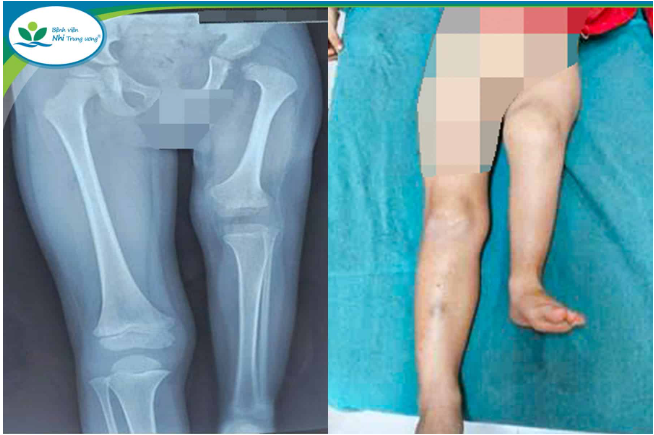

Tại Bệnh viện Nhi Trung ương, thời điểm nhập viện xương đùi trái của trẻ chỉ đạt gần một nửa chiều dài so với bên lành; khớp gối cứng gấp, không thể duỗi hoàn toàn. Khi đặt hai chân song song, bàn chân trái chỉ ngang mức giữa cẳng chân phải, gây chênh lệch chiều dài chi nghiêm trọng và ảnh hưởng lớn đến sinh hoạt hằng ngày.

xoay-cang-chan-2.png

Chân trái của bệnh nhi thời điểm nhập viện - Ảnh BVCC